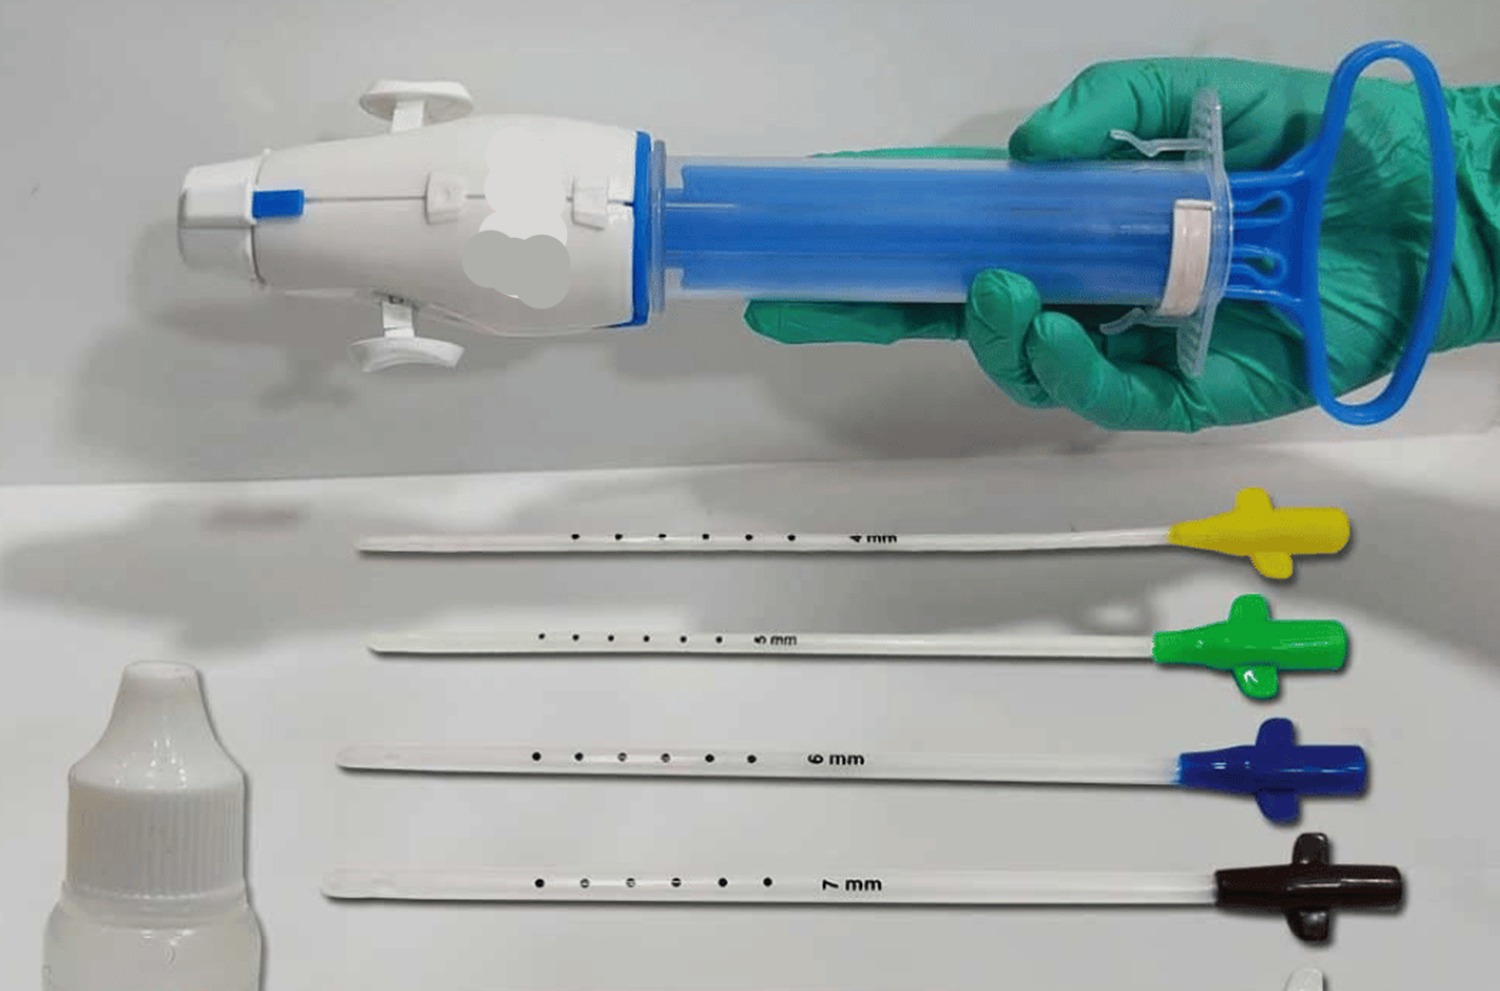

MVA (Manual Vacuum Aspiration)